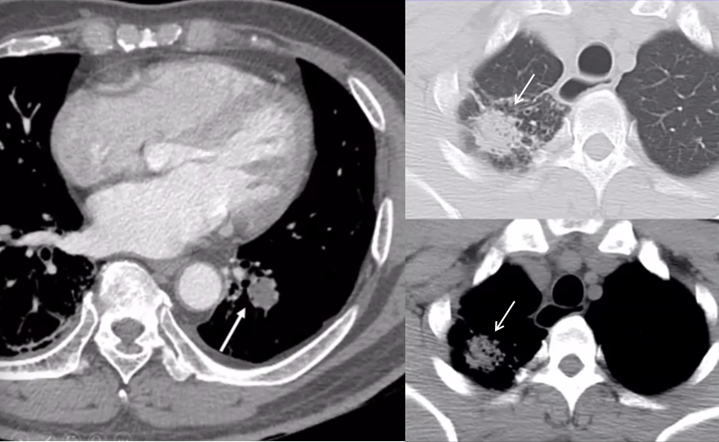

抗感染治疗后病变仍持续进展,斑片状渗出灶范围扩大,并出现实变影,纵隔窗可见密度不均匀,其中分布点状低密度灶(图3)

图片

图3  患者胸部CT(2014-07-26)

即使采取了广泛覆盖革兰氏阴性菌和阳性菌的多药联合的抗感染治疗策略,病变仍然不断进展,周围晕征不断扩大,实变成分增加,内见低密度影(图4)

图4  患者胸部CT(2014-07-31)